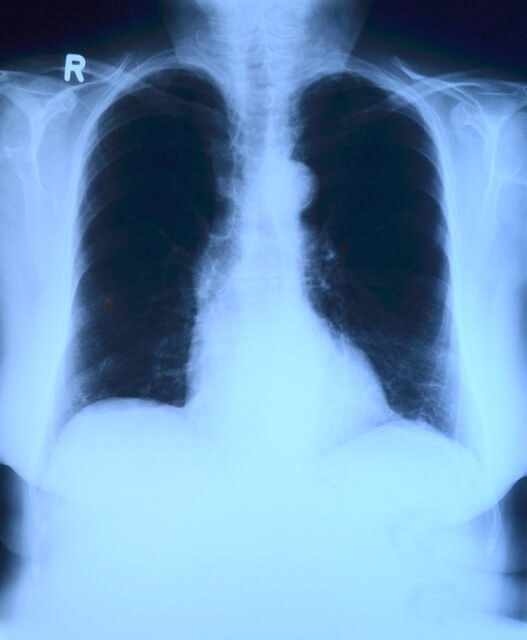

| 기초검사 | 혈압, 혈당, 소변, 혈액검사, 흉부 X-ray, 구강검진 | 20세 이상 | 2년 |